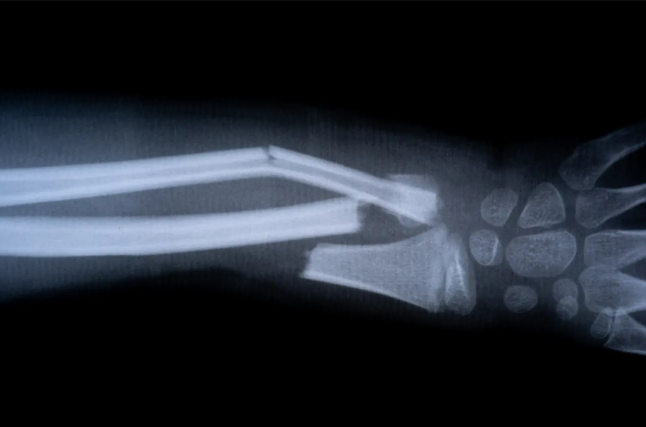

Çinli bilim insanları, kırıkları 3 dakikada iyileştiren 'kemik yapıştırıcısı' geliştirdi!

Çinli araştırmacılar kırık kemik parçalarını 2-3 dakika içinde birbirine bağlayabilen dünyanın ilk 'kemik yapıştırıcısı' malzemesini tanıttı. Bu yeni biyomalzeme, kemik iyileşirken 6 ay içinde emiliyor.